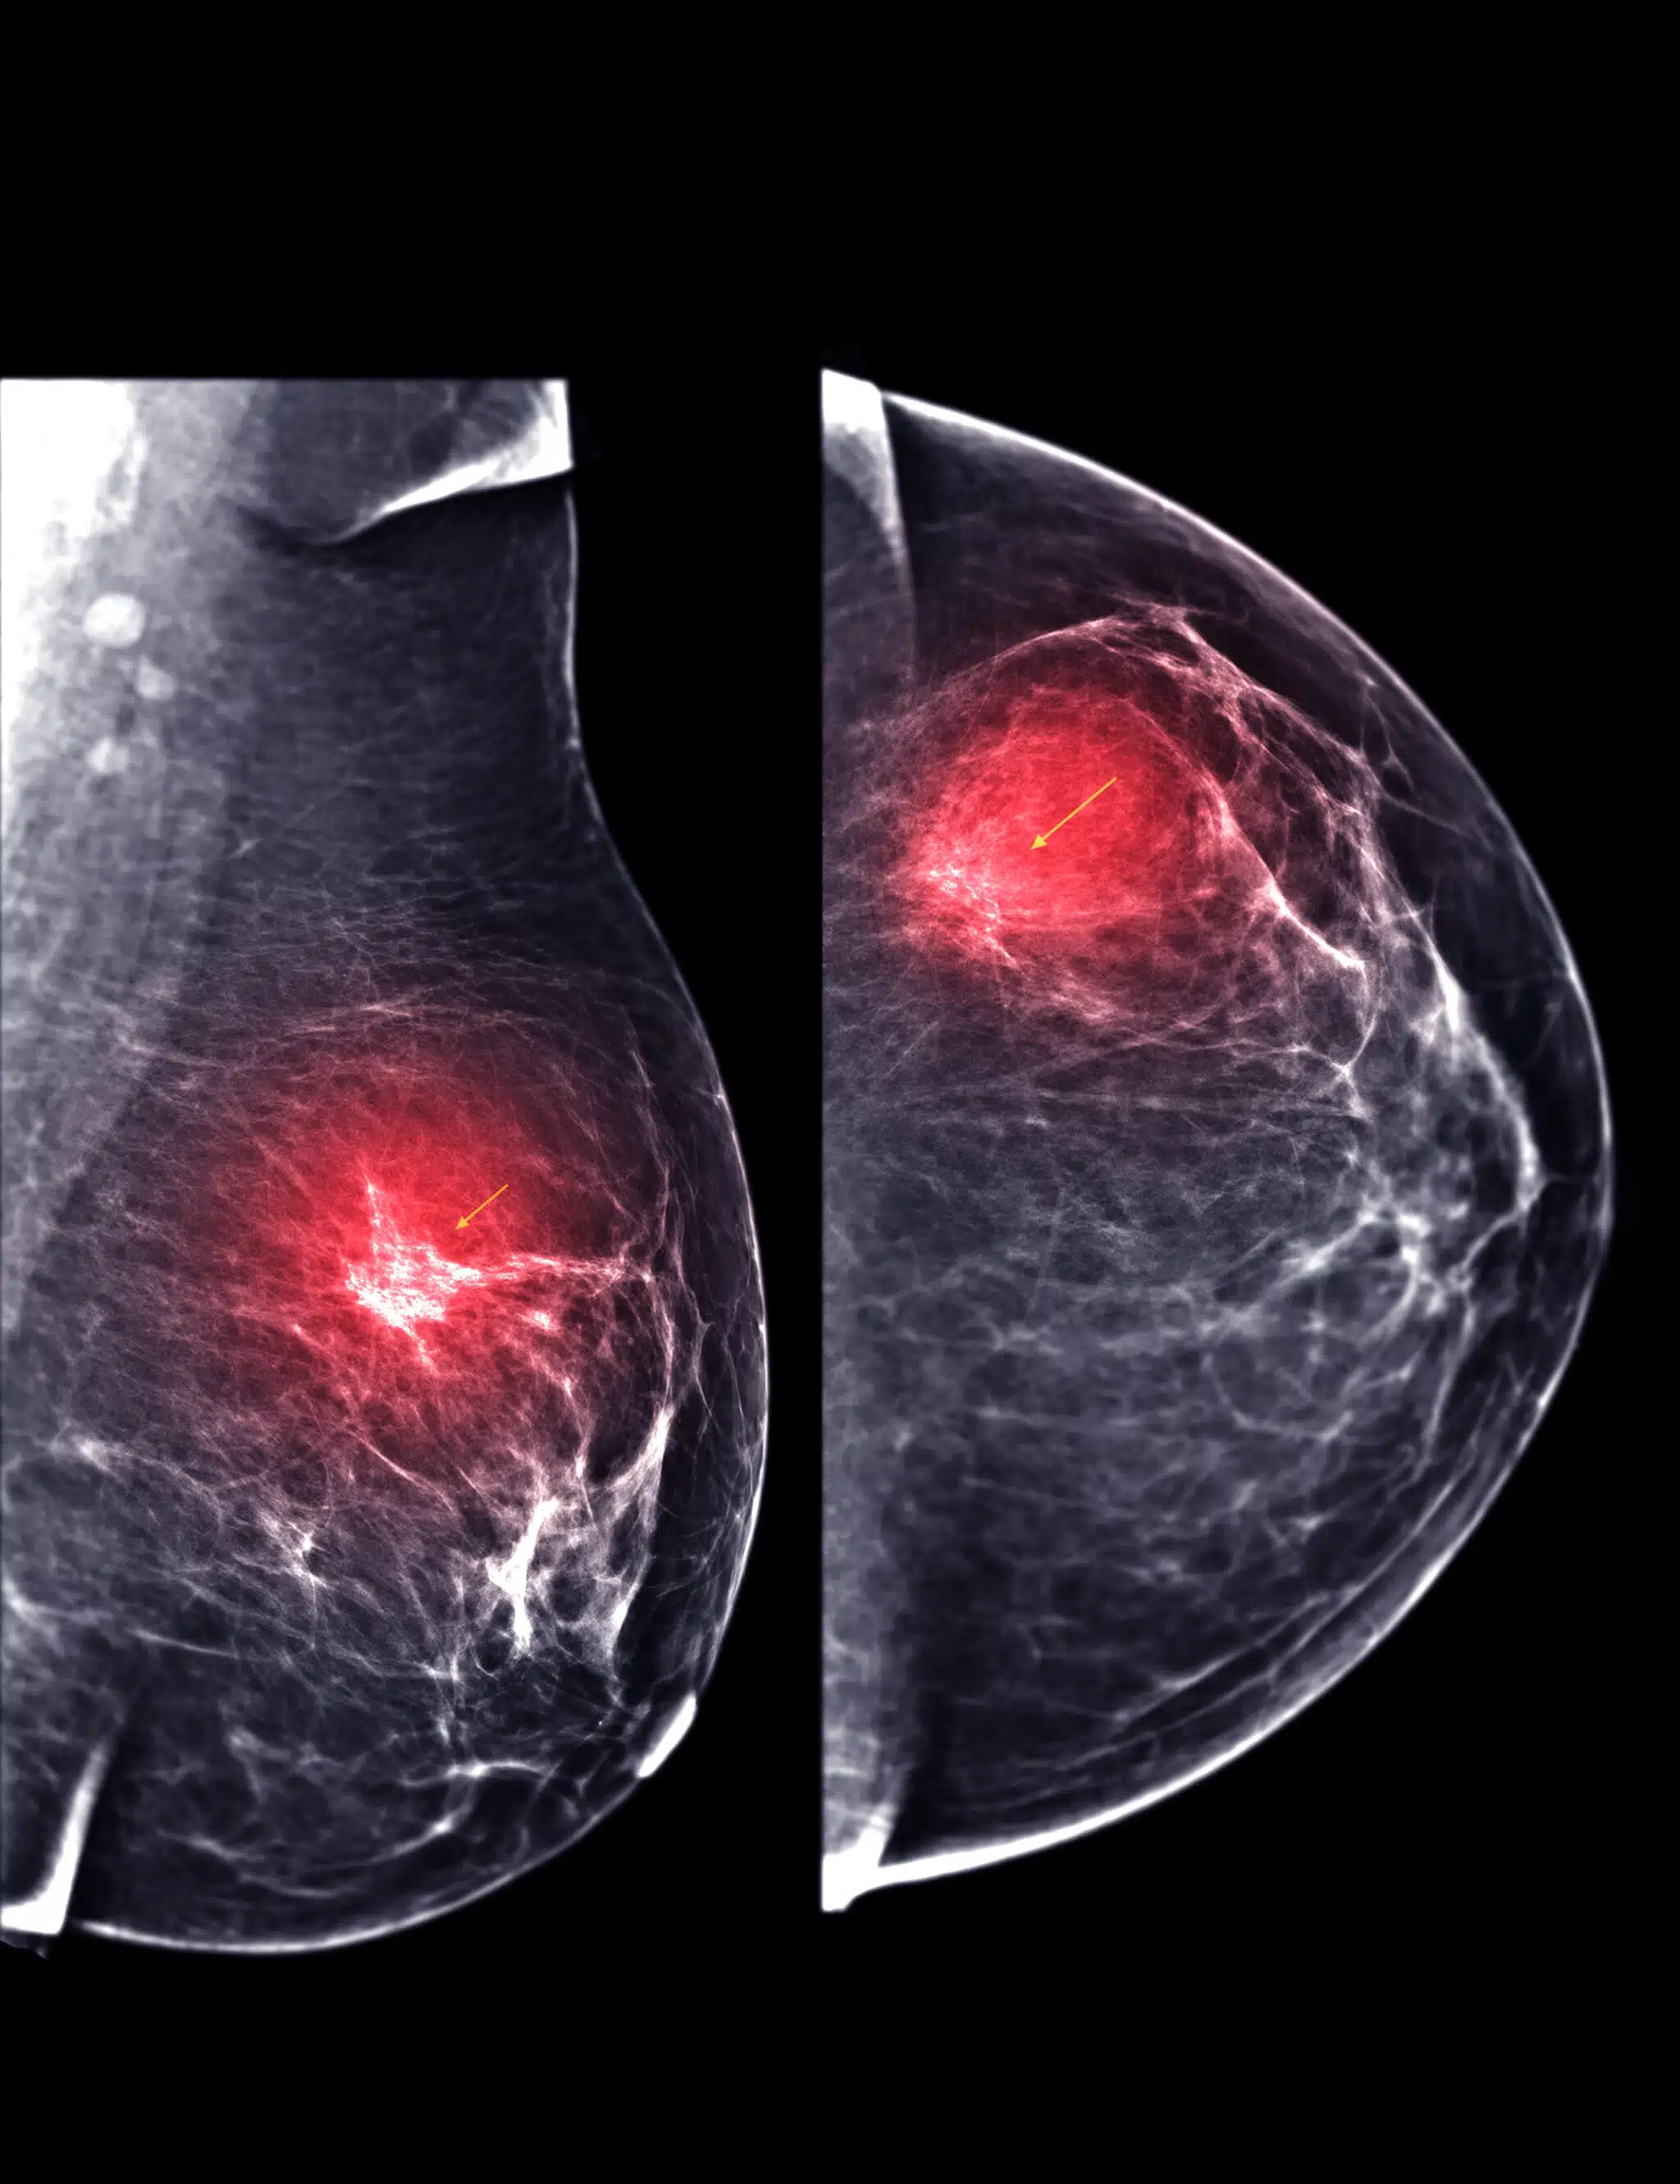

Hologic’s I-View software augments this technique by allowing the acquisition of high- and low-energy images in rapid succession and subtracting the background breast tissue to display the contrast-enhanced regions. The solution can optimize image quality and x-ray dose depending on the contrast agents and compression paddles used. Ultimately, the solution gives clinical practitioners more confidence when making diagnoses.

Another benefit of I-View software is the enhanced lesion detection it offers. The tool boosts the contrast and visibility of lesions in the breast tissue across a range of agents, making it easier for radiologists to identify and characterize suspicious findings.